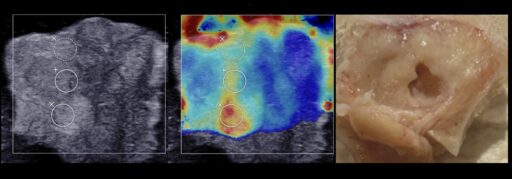

We have also recently demonstrated the feasibility of boiling histotripsy to produce localized mechanical lesions in human prostate cancer samples ex vivo.

Currently, our team is leading the research on a larger sample batch to study the response of various prostate tumors to mechanical fractionation with boiling histotripsy, the influence of their elastic properties on this response, as well as to determine the range of optimal exposure parameters for the effective and rapid fractionation of various prostate tumors.